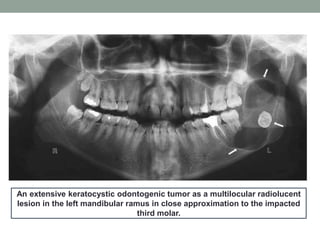

An extensive keratocystic odontogenic tumor as a multilocular radiolucent

lesion in the left mandibular ramus in close approximation to the impacted

third molar.

An extensive keratocysticodontogenic tumor as a multilocular radiolucent lesion in the left mandibular ramus in close approximation to the impacted third molar.